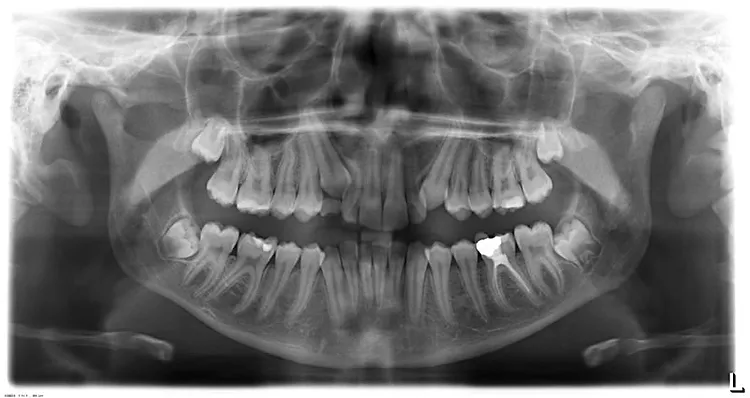

In this case the wisdom teeth were intentionally retained so that healthy molar teeth could be brought into position after extraction(removal) of four decayed molar teeth. Before and after.

Before